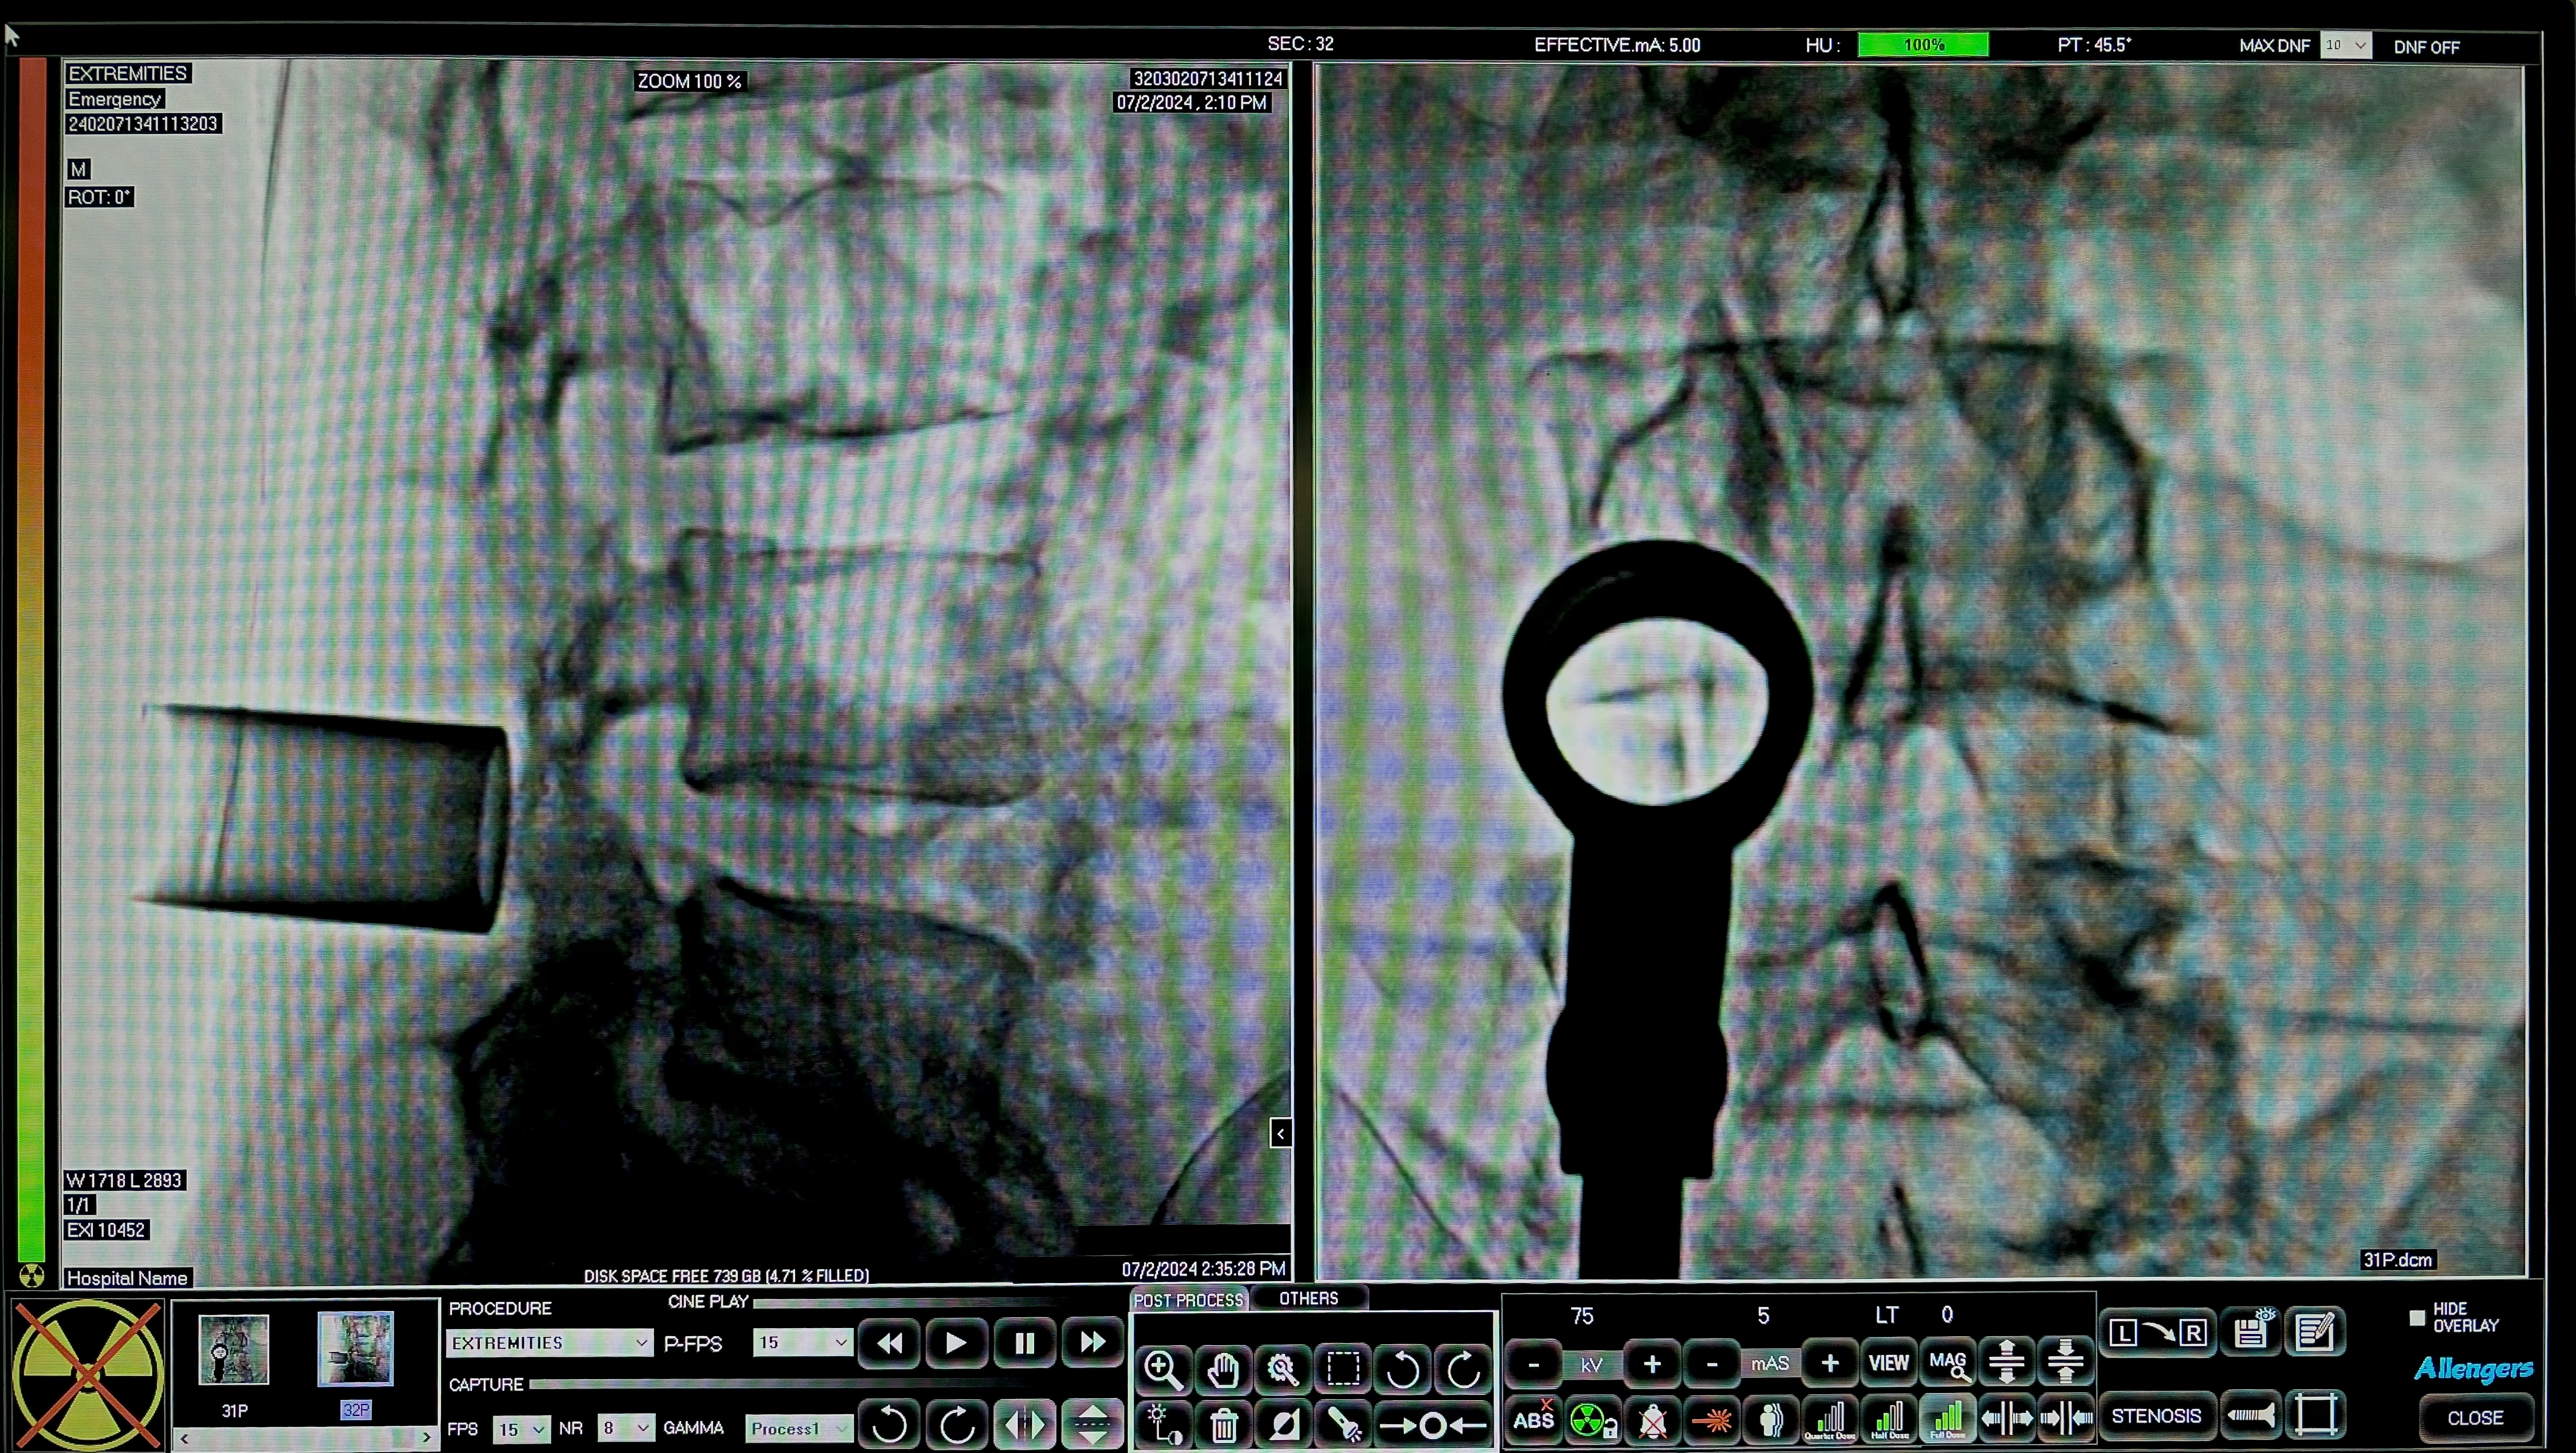

Minimally Invasive Spine Surgery (MISS) or Band Aid Spine Surgery or Key Hole Spine Surgery is a technique wherein Spine Surgery is done through keyholes using tubes under X-ray guidance. Since its introduction, MISS has been accepted the world over as an effective alternative to open spine surgery. As compared to the traditional open spine surgery the minimally invasive spine surgery offers multiple benefits and also decreases the amount of complications associated with open spine surgeries.

Now, we are able to perform more and more complex spine surgeries using MISS techniques. No external stitches are required for the ‘keyhole’ incisions and they are so small that a dressing with an ordinary band-aid may be sufficient, hence the name Band Aid Spine Surgery. The scars left behind after KeyHole Spine Surgery are much less noticeable and are cosmetically acceptable to the patient. We can treat slip disc, spondylolisthesis, lumbar canal stenosis, spinal fractures, spinal tuberculosis & spinal tumors by minimally invasive spinal surgery. MISS is more expensive than open spine surgery and needs specialized equipment like tubes and microscope. We can perform lumbar fusion, Transforaminal Lumbar Interbody Fusion (TLIF), spine fracture fixation and Lumbar Decompression using MISS techniques without a big midline incision as required in traditional open spine surgery.